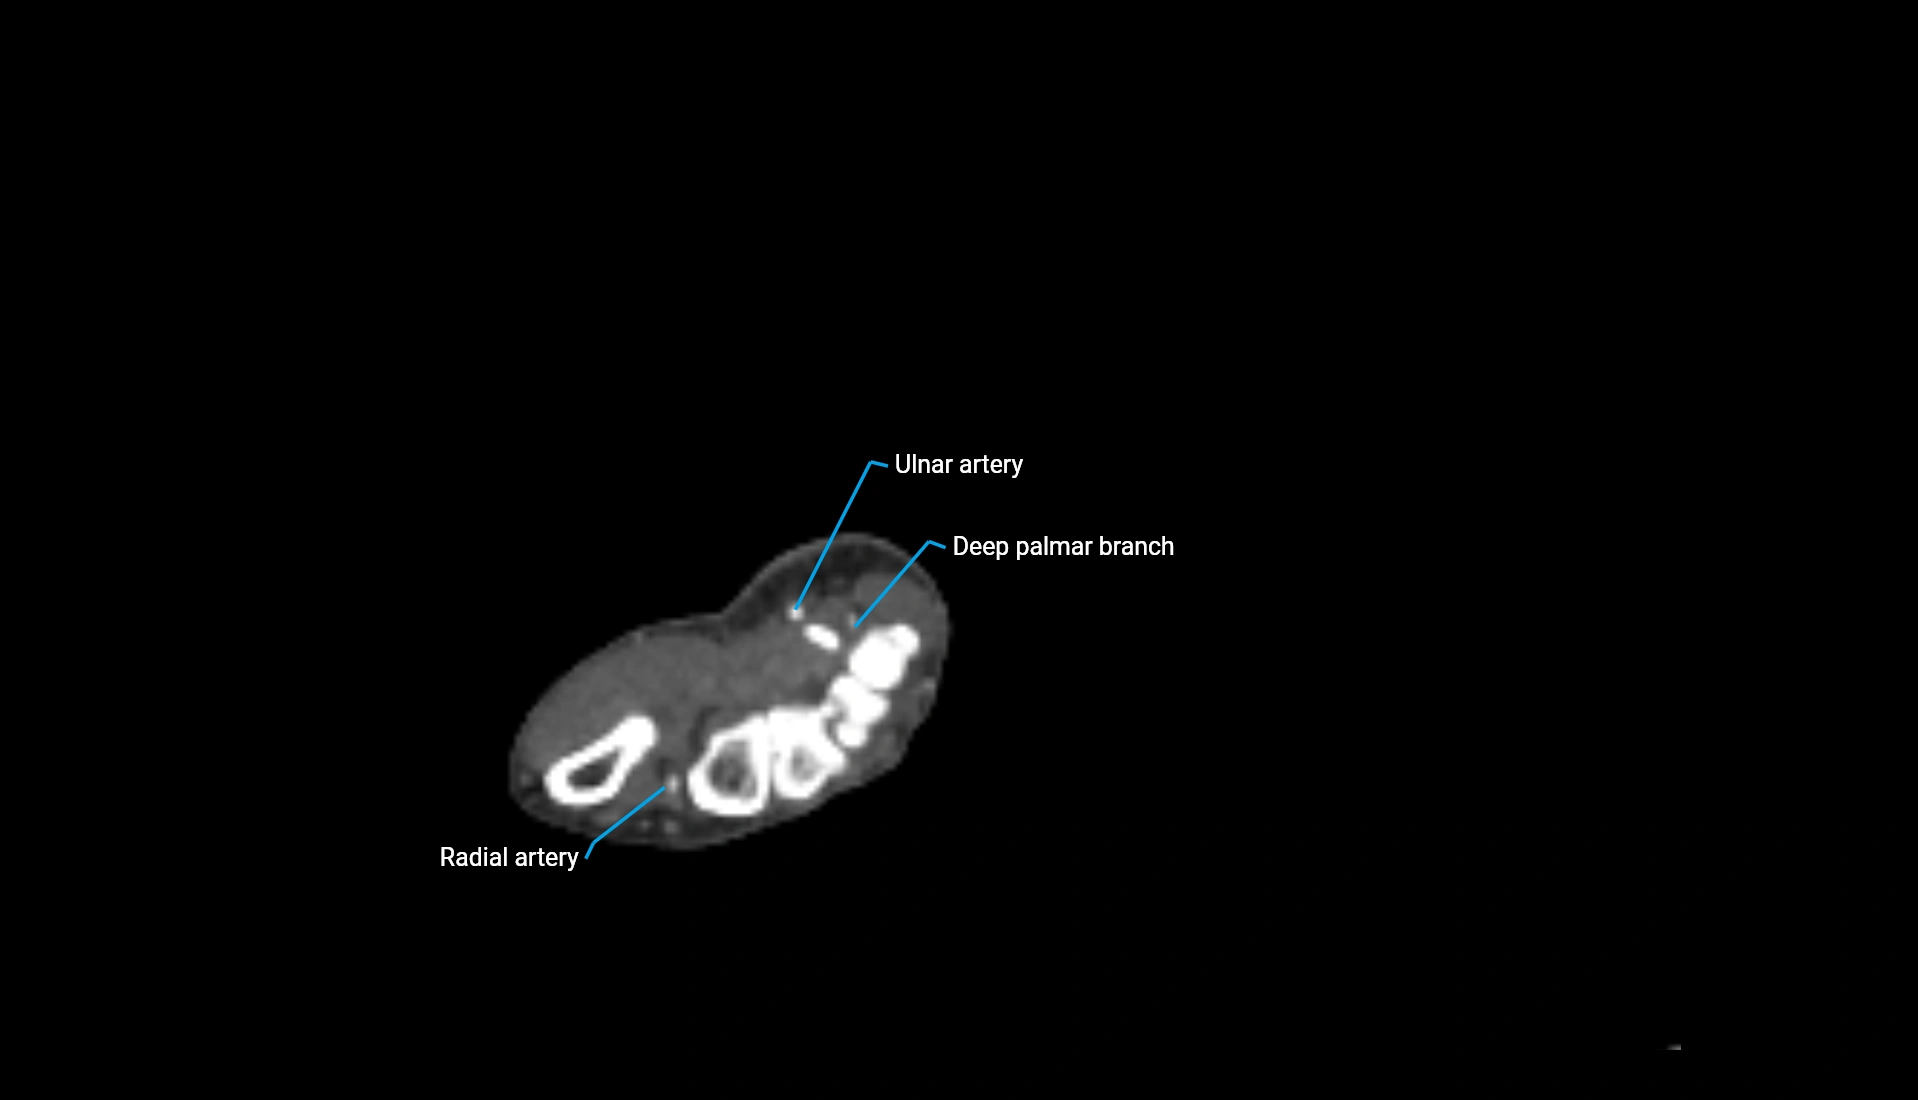

CT Appearance

Non-Contrast CT:

• Cortex: High-density, sharply defined

• Subchondral bone: Dense cancellous matrix

• Articular surface: Smooth concave contour articulating with the capitellum

• Excellent for evaluating bone integrity, alignment, and subtle fractures